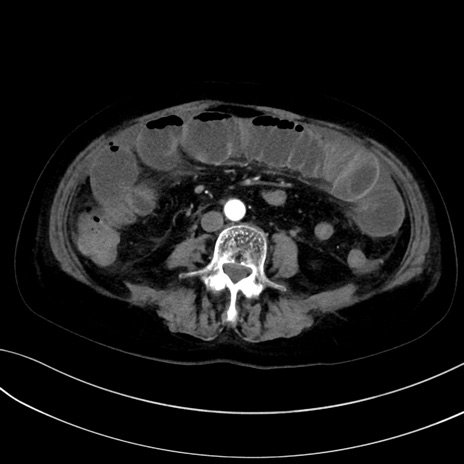

症例13 CT(横断像)1日半後